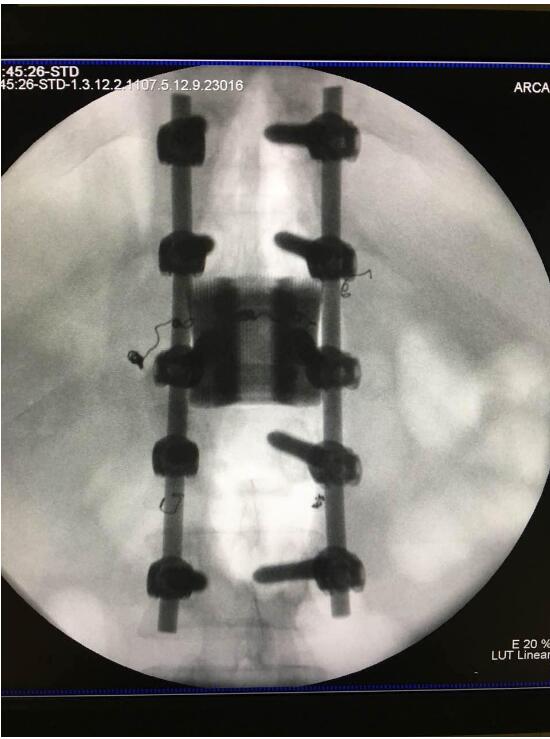

2018年2月7日華鈦三維與南方醫(yī)院脊柱骨外科聯(lián)合澳大利亞技術(shù)科學(xué)與工程院吳鑫華院士領(lǐng)導(dǎo)的莫納什大學(xué)增材制造研究中心合作的世界第一例3D打印個性化“人工椎體/椎間盤一體化“植入手術(shù)成功實(shí)施。不僅保住了病人的脊椎,還保住了其日后的活動能力。

這次手術(shù)是廣州華鈦三維骨科研究中心(華鈦三維骨科研究院)與南方醫(yī)院聯(lián)合澳大利亞技術(shù)科學(xué)與工程院吳鑫華院士領(lǐng)導(dǎo)的莫納什大學(xué)增材制造研究中心合作的世界第一例3D打印個性化人工椎體/腰間盤一體化植入手術(shù)。南方醫(yī)院脊椎及骨病外科鄭明輝副主任醫(yī)師在嶺南名醫(yī)陳建庭主任和朱青安教授指導(dǎo)下,與華鈦三維工程師陸國贊合作構(gòu)思設(shè)計(jì),澳大利亞莫納什大學(xué)增材制造研究中心主任吳鑫華院士團(tuán)隊(duì)進(jìn)行了一個多月的個性化鈦合金3D打印工藝研究,成功打印出符合病人要求的人工椎體/腰間盤一體化植入物。這次手術(shù)的成功,標(biāo)志著中國的3D打印植入物技術(shù)在骨科醫(yī)療領(lǐng)域達(dá)到世界先進(jìn)水平。

為了更好的完成手術(shù),陳建庭主任、鄭明輝副主任醫(yī)師等骨科專家與華鈦三維的3D打印專家從2017年10月份開始籌備該手術(shù)。考慮到每一個病人的脊椎形狀都存在差異,骨科專家認(rèn)為用一個現(xiàn)成的標(biāo)準(zhǔn)植入物不大可能匹配病人的生理參數(shù)。醫(yī)學(xué)專家和3D打印專家根據(jù)病人脊柱的CT掃描數(shù)據(jù),為病人的脊柱建立了精準(zhǔn)的3D圖像。根據(jù)這個圖像,治療團(tuán)隊(duì)就能夠設(shè)計(jì)并定制出屬于病人的個性化植入物。為了使個性化定制的人工椎體與病人椎體之間更好的融合,手術(shù)實(shí)施前治療團(tuán)隊(duì)先后設(shè)計(jì)了100多個方案,制作了數(shù)十個植入物的術(shù)前模型進(jìn)行研討。事實(shí)證明,手術(shù)最終使用的植入物是最適合手術(shù)和病人身體情況的。

利用3D打印技術(shù)生產(chǎn)出來的人工椎體是完全按照患者的解剖結(jié)構(gòu)完成脊椎結(jié)構(gòu)重建及固定的, 裝上一枚精準(zhǔn)的、個性化的人工脊椎,患者康復(fù)后完全可以正常地生活和工作。過去這種手術(shù)常常是使用鈦網(wǎng)內(nèi)填入自體或異體碎骨作為椎體間支撐材料,但鈦網(wǎng)一旦移位壓迫脊髓,患者就會有癱瘓的風(fēng)險(xiǎn)。這次手術(shù)中的脊椎植入物內(nèi)部具有經(jīng)過力學(xué)優(yōu)化設(shè)計(jì)的晶格結(jié)構(gòu),比傳統(tǒng)鈦網(wǎng)具有更強(qiáng)的承重力,金屬3D打印可以直接制造出這樣的復(fù)雜結(jié)構(gòu)。

最終在經(jīng)歷近八個小時后,病人的家屬終于等到了好消息:人工椎體/椎間盤一體化金屬植入物成功植入,手術(shù)順利。由于病人術(shù)中出血量小,生命體征平穩(wěn),他不用進(jìn)入ICU觀察,直接回到了普通病房?!艾F(xiàn)在我們都很高興,成功做出了世界首例人工椎體/椎間盤一體化金屬植入物,病人今后可以與常人一樣工作和生活?!编嵜鬏x醫(yī)生說。